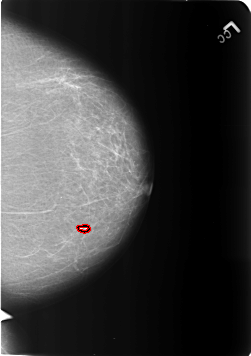

B_3211_1.LEFT_CC

LEFT_CC LINES 5696 PIXELS_PER_LINE 4008 BITS_PER_PIXEL 12 RESOLUTION 50 OVERLAY

FILE: B_3211_1.LEFT_CC.OVERLAY

TOTAL_ABNORMALITIES 1

ABNORMALITY 1

LESION_TYPE CALCIFICATION TYPE COARSE DISTRIBUTION N/A

LESION_TYPE MASS SHAPE OVAL MARGINS CIRCUMSCRIBED

ASSESSMENT 2

SUBTLETY 5

PATHOLOGY BENIGN_WITHOUT_CALLBACK

TOTAL_OUTLINES 1

BOUNDARY